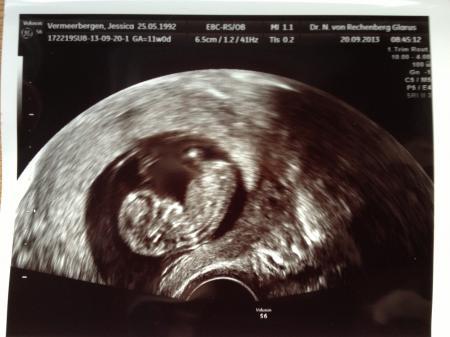

Hallo Ihr Lieben, Ich bin wieder zurück vom FA termin und es war wundervoll Ich war heute das erste mal dort und ich muss sagen ich hab noch nie so einen tollen Arzt gesehen :) wow! Ein Opi der Ahnung hat und sehr lieb und einfühlsam war. Es hat nichts weh getan ;) So jetzt komme ich zu unserem Schatz :))) Es ist perfekt entwickelt auf den Tag genau und 4,3 cm groß. Es ist alles schon angelegt:) ich habe sogar Knochen gesehen und das Gesicht :) Nackenfaltenmessung wurde auch gemacht die war sehr unauffällig. 1,4 mm glaube ich. Das kleine hat sich viel bewegt und kräftig mit Armen und Beinen gewunken :) das ist das schönste Gefühl gewesen :) Wir sind sehr glücklich und genießen ab jetzt die ss in allen Zügen :)